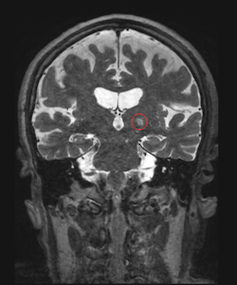

One rare disease of particular interest for my lab is cerebral cavernous malformation, or CCM . CCMs are lesions in the brain that occur when the cells that make up blood vessels undergo uncontrolled growth. While uncommon, when these lesions grow and hemorrhage, they can cause debilitating neurological symptoms . The most common treatment for CCM is surgical removal of the brain lesions; however, some CCMs are located in brain areas that are difficult to access, creating a risk of side effects. Radiation is another treatment option, but it, too, can lead to serious adverse effects.

We found that using focused ultrasound to open the blood-brain barrier can improve drug delivery to CCMs . Additionally, we also observed that focused ultrasound treatment itself could stop CCMs from growing in mice, even without administering a drug. While we don't yet understand how focused ultrasound is stabilizing CCMs, abundant research on the safety of using this technique in patients treated for other conditions has allowed neurosurgeons to begin designing clinical trials testing the use of this technique on people with CCM.